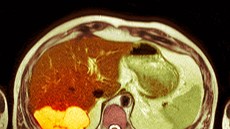

Jakmile je rakovina jater diagnostikována, přistupuje se k léčbě podle toho, jak velký je nádor a v jakém stavu jsou játra. Pokud je nádor zachycen včas, může být odstraněn chirurgicky. U vybraných pacientů je možné provést transplantaci jater, která zajišťuje nejlepší dlouhodobé výsledky.

Pokud operace není možná, využívají se metody, které ničí nádorové buňky cíleně — například radiofrekvenční ablace nebo chemoembolizace, kdy se nádor „přidusí“ tím, že se uzavřou cévy, které ho vyživují. U pokročilých stadií se používá systémová léčba, která může průběh onemocnění zpomalit, i když jej už nedokáže zcela vyléčit.